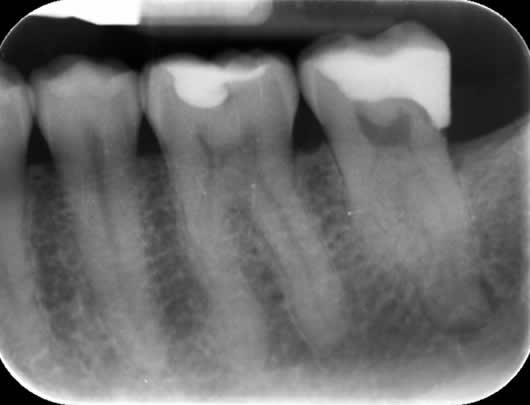

Case 2: Root canal treatment – the elusive MB2 canal.

In approximately 90% of upper first molars there are four root canals. The fourth canal (MB2) is difficult to locate and can be very challenging to negotiate to its end. It is a very common occurrence that this canal is missed during treatment and this can lead to failure. We use a dental microscope, which magnifies the tooth and assists us in locating this canal. We then use a series of tiny instruments in a specific technique, honed over many hours of practice, to negotiate to the end of the canal. This case shows the filling of all four canals.

Pre-operative radiograph UR6

Post-operative radiograph UR6